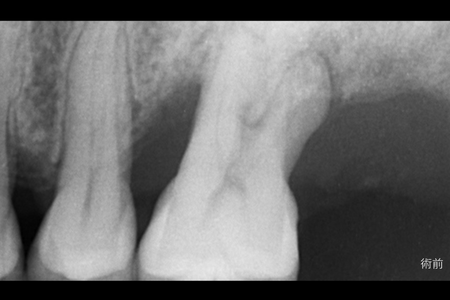

治療名 【重度歯周病】歯周組織再生療法による機能回復 治療期間 約1年(初期治療・経過観察期間含む) 執刀医 Dr. 大杉 治療費 250,000円(税込) 治療解説 一般的に抜歯適応と診断されやすい状態でしたが、歯の保存を優先して歯周組織再生療法を行いました。

事前にプラークコントロールと歯石除去を徹底し、炎症を安定させたうえで外科処置を実施。

結果として抜歯を回避し、長期的な機能維持を目指せる状態へ改善しました。リスク・副作用 術後に一時的な腫れや痛みが生じることがあります(鎮痛剤等の処方で管理を行います)。

また、喫煙等の生活習慣によっては治癒不全のリスクが高まる場合があります。 -